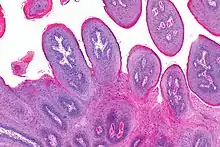

![]() | Helminth in appendix | Micrograph showing lumen of appendix and cut section of pin worm. | Category: Histopathology of appendix with Enterobius vermicularis | Parasitic helminthiasis infectious disease |